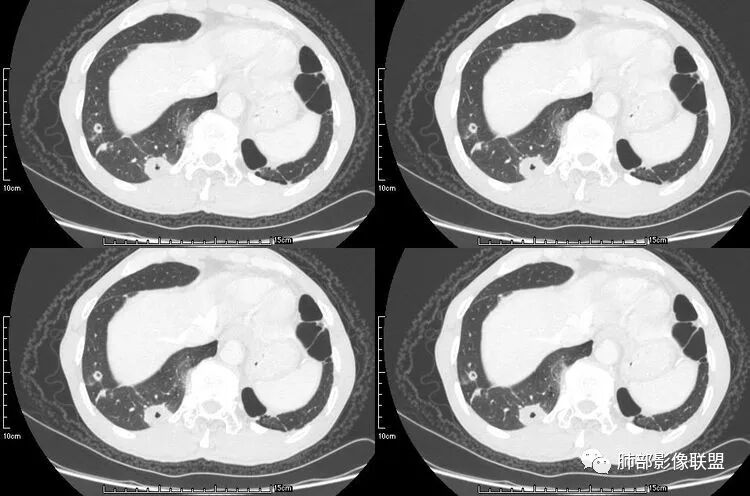

肺腺癌伴双肺转移,双肺多发环形薄壁囊腔转移瘤;

来源于南京大学医学院鼓楼医院 周科峰

病例二

颈部淋巴结病检:腺癌;双肺多发薄壁囊腔性转移瘤;

来源于南京市第一医院 吴婧